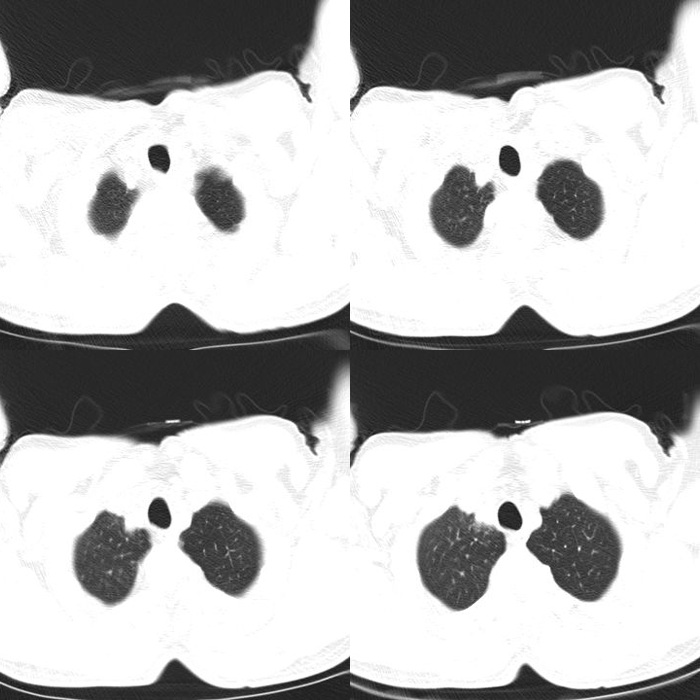

CT51038:M68y,肺部疑难病例请会诊!

68岁男性,刺激性干咳数月。 其他检查: 1.较本院5个月前片对比,病灶明显增多,旧片实变仅出现在右肺中叶外侧段。 2.患者近5个月内查了3次CEA,CEA:正常。 3.患者近5个月内查了3次CA199,按时间分别为:2016.35;14 ...

双肺可见多发斑片斑块结节密度增高影,部分病灶内见低密度影,似蜂窝状,部分病灶似磨玻璃状,右侧胸腔背侧见液体密度影,考虑肺泡癌可能性大,机遇性感染?

双肺见多发斑片斑块结节状密度增高影,部分病灶内见低密度影,似蜂窝状,部分病灶呈磨玻璃影,右侧胸腔见液体密度影。考虑:肺泡癌可能性大,机遇性肺炎?

双肺斑片状、结节状密度影、边界不清、考虑霉菌感染、带除外支气管肺泡癌

双肺内见斑片状,结节状病灶,密度不均匀,边界模糊,其内见数个小透光区,纵膈内无明显肿大淋巴结。1.机遇性感染。2、继发性肺结核。3、肺泡癌待出外。

一般的炎症早好了,比较支持肺泡癌。典型的临床表现是咳嗽,可大量白色泡沫样谈,静置后分层,胸闷。

肺泡癌,不过现在的提法是叫肺腺癌